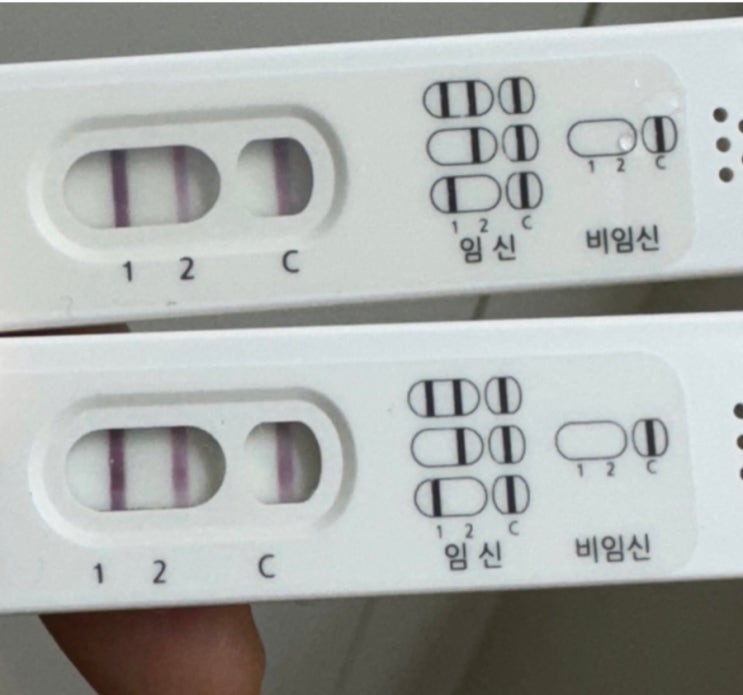

임신일기) 6주차 _ 강동구보건소 임산부선물, 비오템튼살크림, 튼살오일, 풀리오 무선다리마사지기

아기 심장소리도 듣고 했으니 카테고리를 임신일기로 변경해 보았다☺️ 내가 다녔던 난임병원 원장님께서...